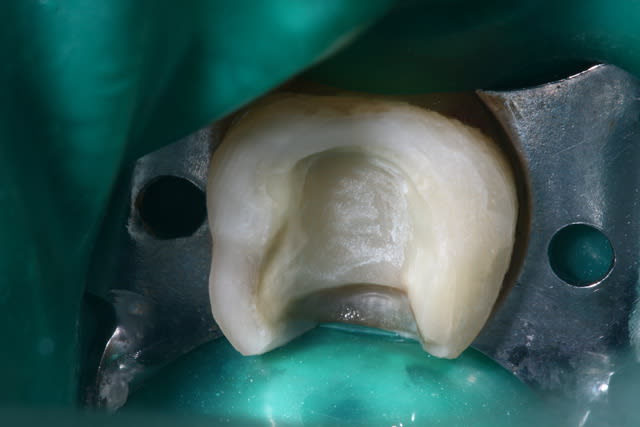

Photo 1. Moi: "Voilà pourquoi il vous faut un onlay."

Photo 3. Le patient: "Ah quand même! Ben on va faire les autres alors!"

pour les excès, le composite classique chauffé a beaucoup d'avantage pour coller les onlays. On a tout le temps de retirer les excès qui deviennent pâteux, plastique.

Je colle depuis quelque temps au compo de restauration (Tetric classic) chauffé dans un réchauffe carpule et vibré au US.

J'utilise ce protocole pour:

- La facilité à retirer les excès

- La qualité mécanique et esthétique du joint

- les propriétés mécanique de ce collage

Il faut bien sur associer un adhésif... j'utilise un MR2, Adper Single Bond de 3m avec mordançage total ou

De plus en plus quand je peux, je fais un IDS, collage immédiat le jour de la préparation avant empreinte... avec de l'optibond FL qui reste un gold standard...

Il faut savoir que la qualité du collage joue dans la résistance mécanique de l'onlay.

Le matériaux de choix c'est aujourd'hui l'Emax/empress....